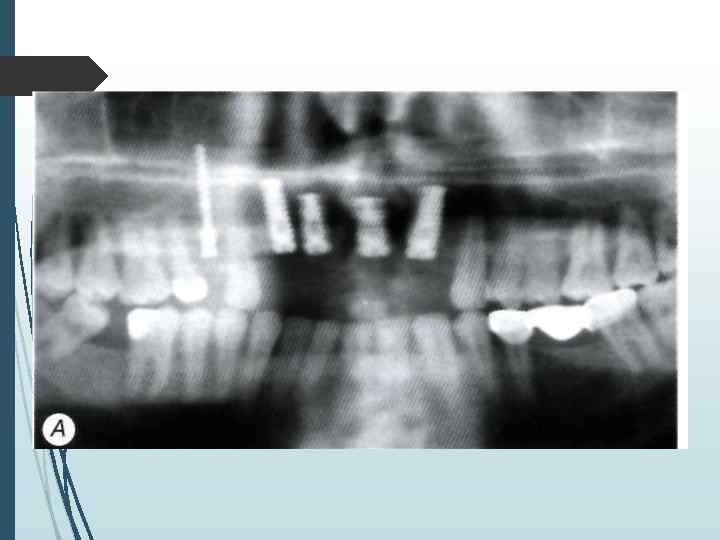

Двухэтапная методика имплантации I этап Произведя разрез и отслойку слизието-надкостничных лоскутов, приступают к формированию костного ложа иод имплантат с использованием общепринятых принципов атравматнчного препарирования кости. Сверлом диаметром неболее 2 2. 5 мм препарируют направляющий канал в кости на глубину, соответствующую высоте внутрикостного элемента (рис. 11 -2. 11 -3). Формирование направляющего канала необходимо для создания ориентиров расположения и направления вертикальной оси устанавливаемого имплантата. Затем этот канал расширяют при помощи сверла, диаметр которого не превышает 3 -3, 5 мм. Если диаметр внутри костной части имплантата составляет более 3. 5 мм, производят дополнительное препарирование сверлом соответствующего диаметра.

А препарирование направляющего канала фрезой Линденмана диаметром 2, 3 мм; 6 — расширение направляющего канала фрезой диамефом 3, 5 мм: В — расширение ложа фрезой диаметром 4. 0 мм:

Г — окончательное формирование ложа метчиком: Д установка внутрикостного элемента; Е установка винта-заглушки внутрикостно!о элемента:

Ж — закрытие операционной раны